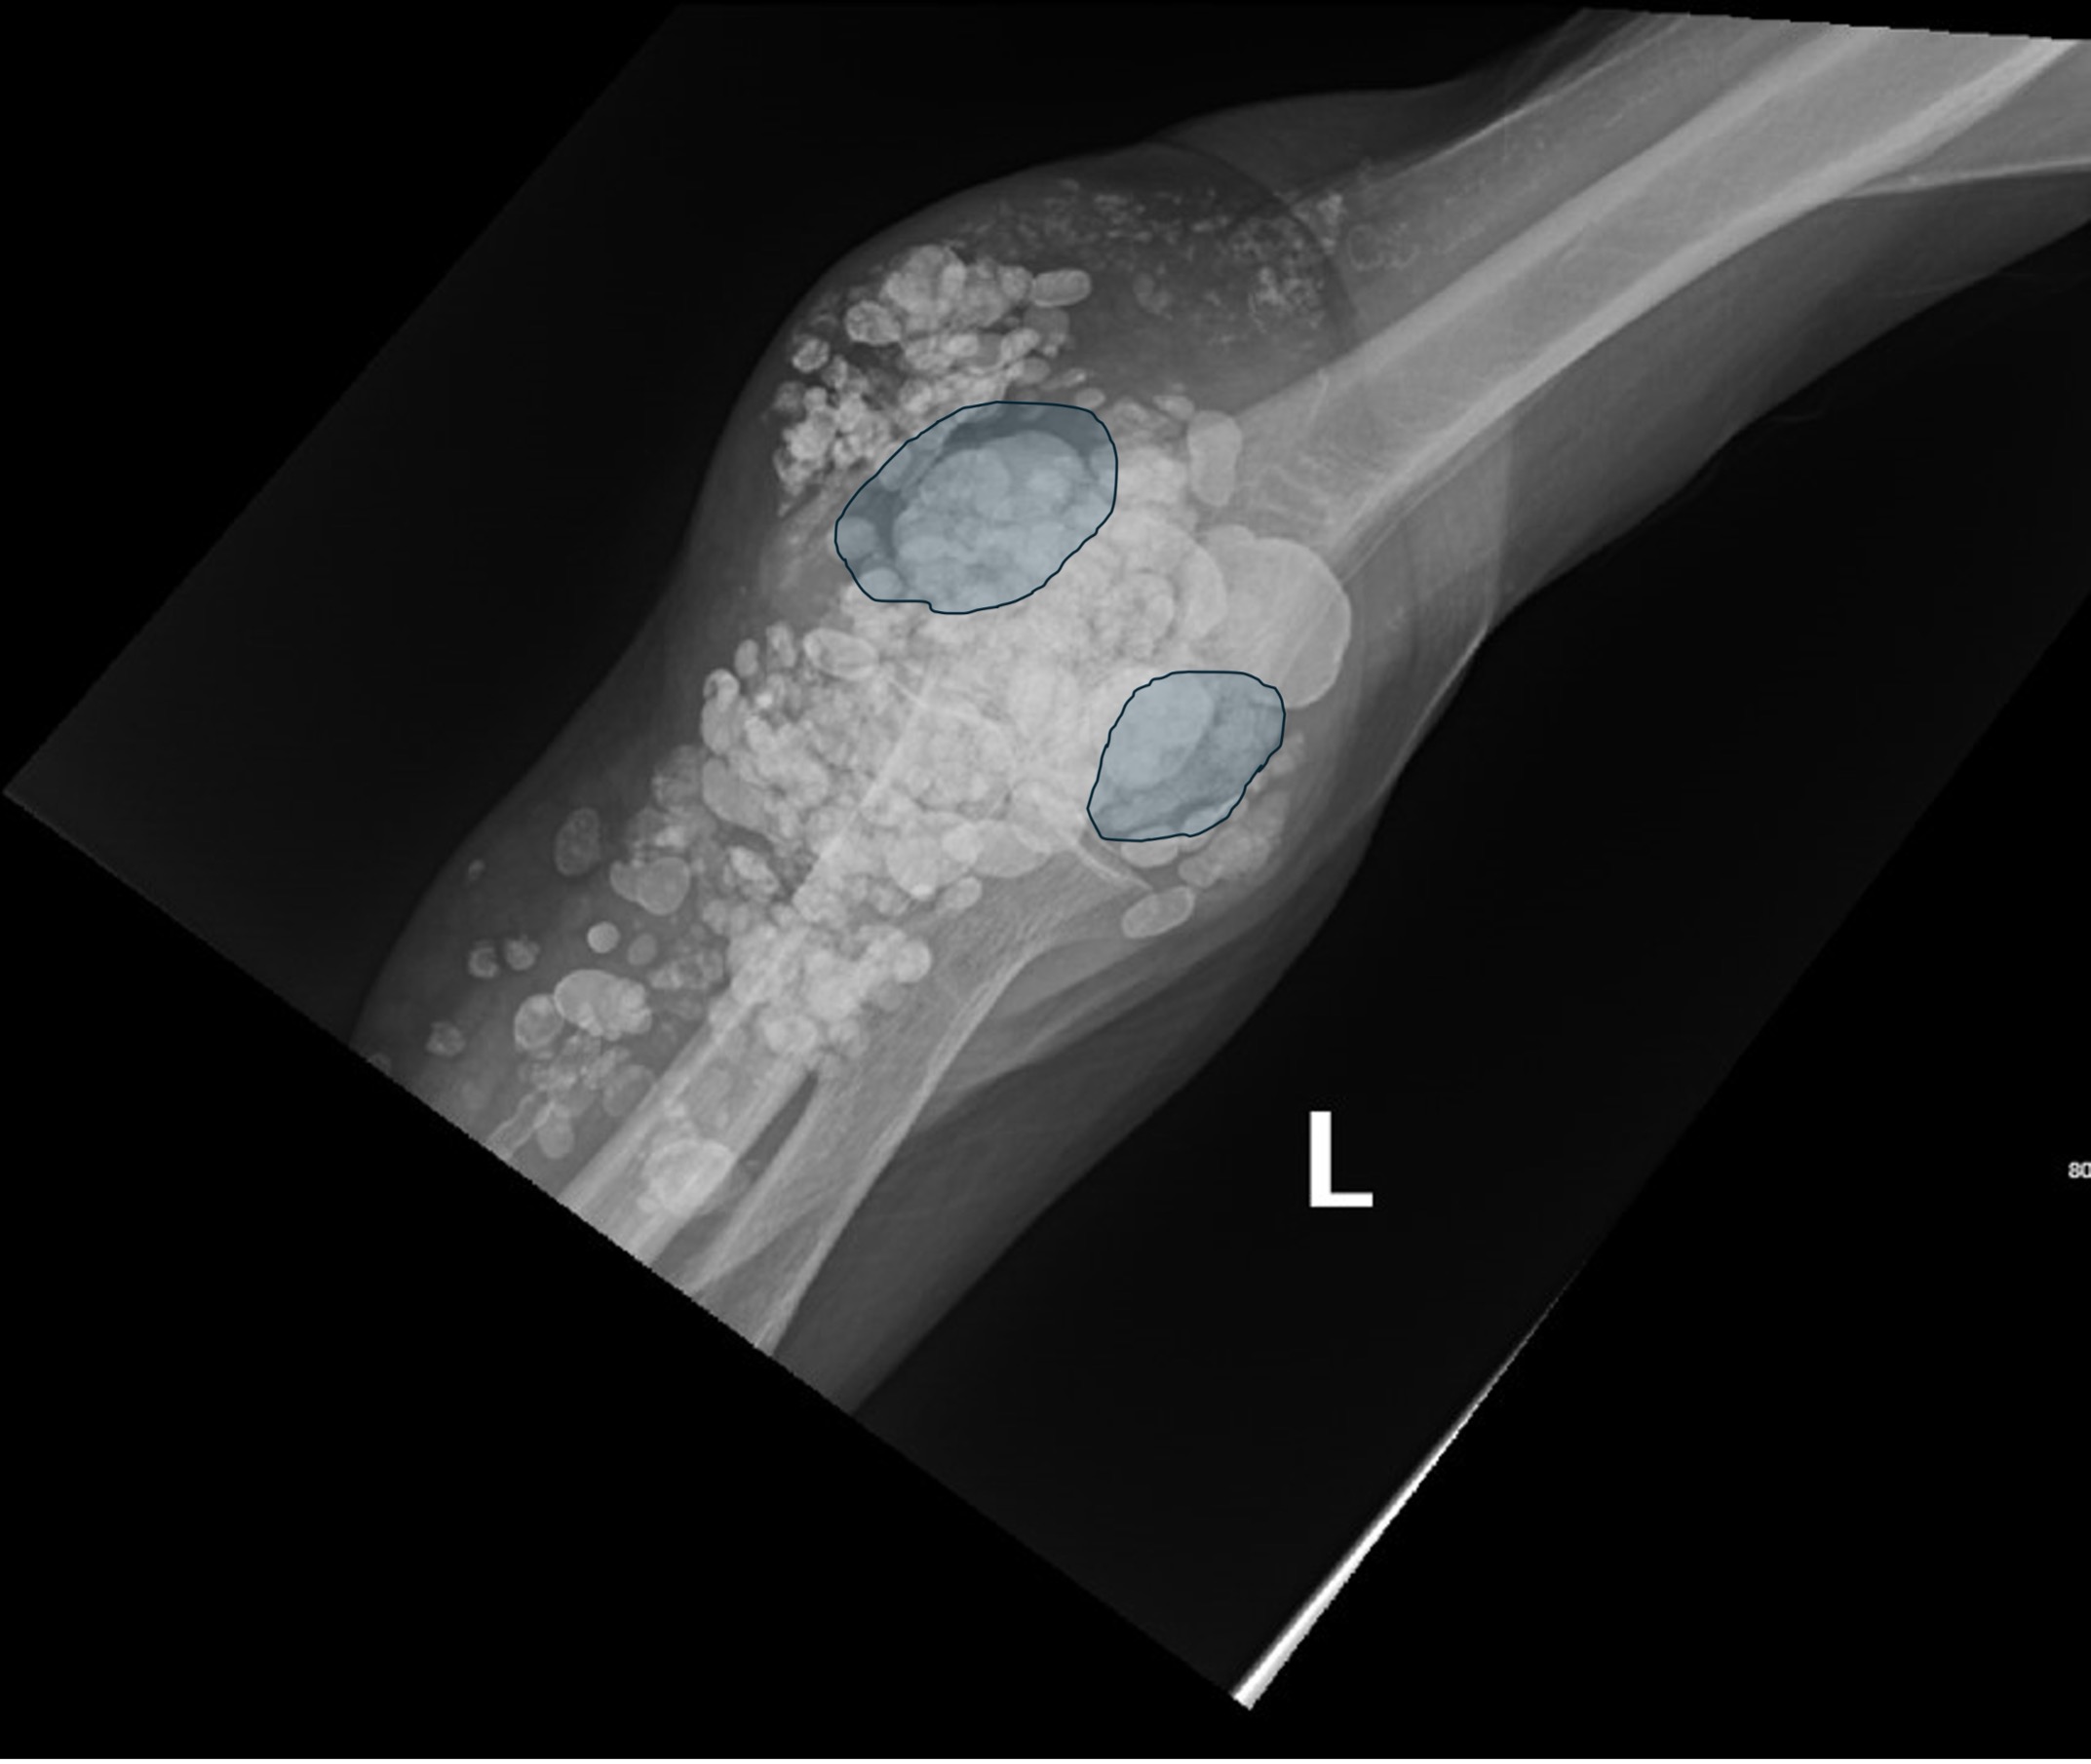

Calcinosis cutis is a condition in which calcium-phosphate salt deposits are formed in cutaneous and subcutaneous tissue. A subtype, metastatic calcinosis cutis, can occur in patients with disorders that cause hypercalcemia or hyperphosphatemia such as end stage renal disease. We present a case of a 67-year-old man with end-stage renal disease (ESRD) on dialysis who presented to the emergency department with a draining left elbow wound. On exam, he had irregular, firm nodules palpable in the subcutaneous tissue of both large and small joints. The presence of calcinosis cutis on imaging and lack of other findings suggesting infection led to outpatient wound care treatment. Recognizing the appearance of calcinosis cutis on imaging and conditions that present with calcinosis cutis is important for the emergency physician.

Topics: Calcinosis cutis, end-stage renal disease, ESRD, dialysis, subcutaneous calcifications.